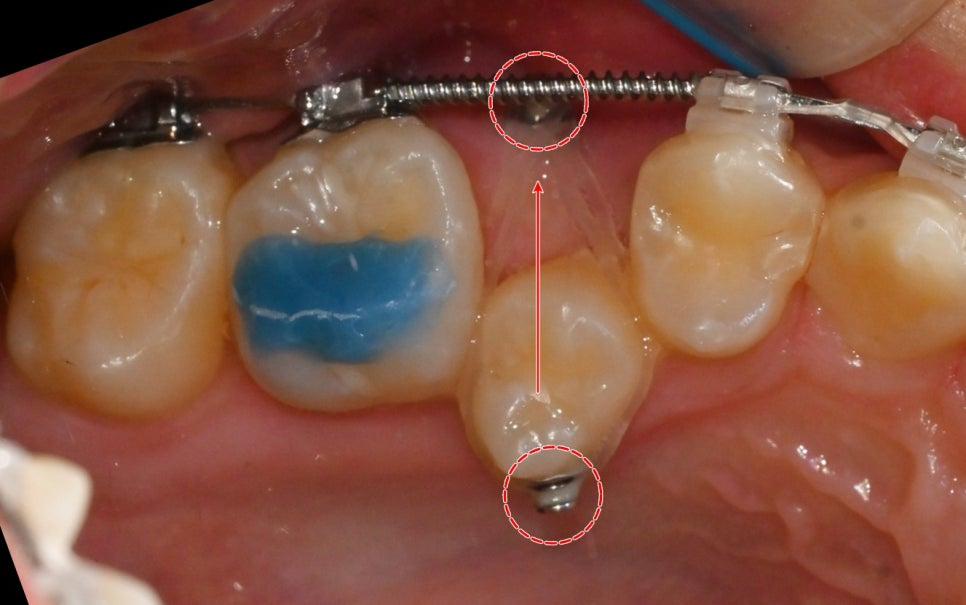

24.01.22

치열이 1차적으로 개선되었을 때

오른쪽 위 작은 어금니가

이동될 수 있는 공간을 만들어 주는데요.

이후 미니 스크류를 식립하여

오픈 코일 스프링으로 인해

오른쪽 전치부의 치열이

이동되지 않도록 고정합니다.

24.05.13

24.09.24

이후 어느 정도 당겨졌다면

브라켓을 부착해

세부 조정을 진행합니다.